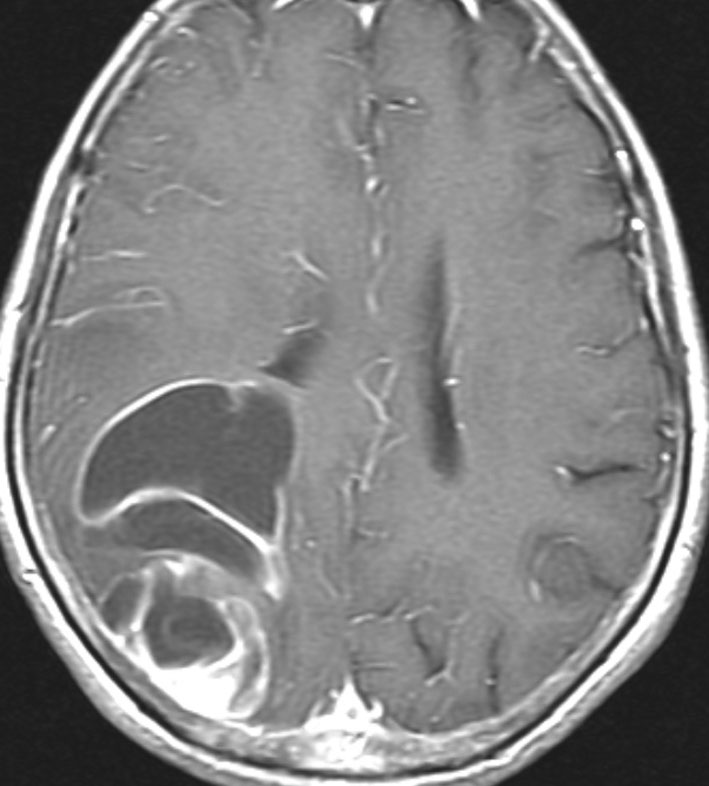

expanding, solid 固形腫瘍的なもの

壊死ではない「のう胞」を伴い,ガドリニウムで強く増強されます。グレード 4 (膠芽腫)と間違えるようなものです。しかし,のう胞はありますが中心壊死がありません。

腫瘍を大部分摘出できるので,積極的な摘出術をして,手術後には放射線化学療法を加えます。この例では,手術後の放射線治療計画の領域が狭ければ,60グレイを使用できる部位です。